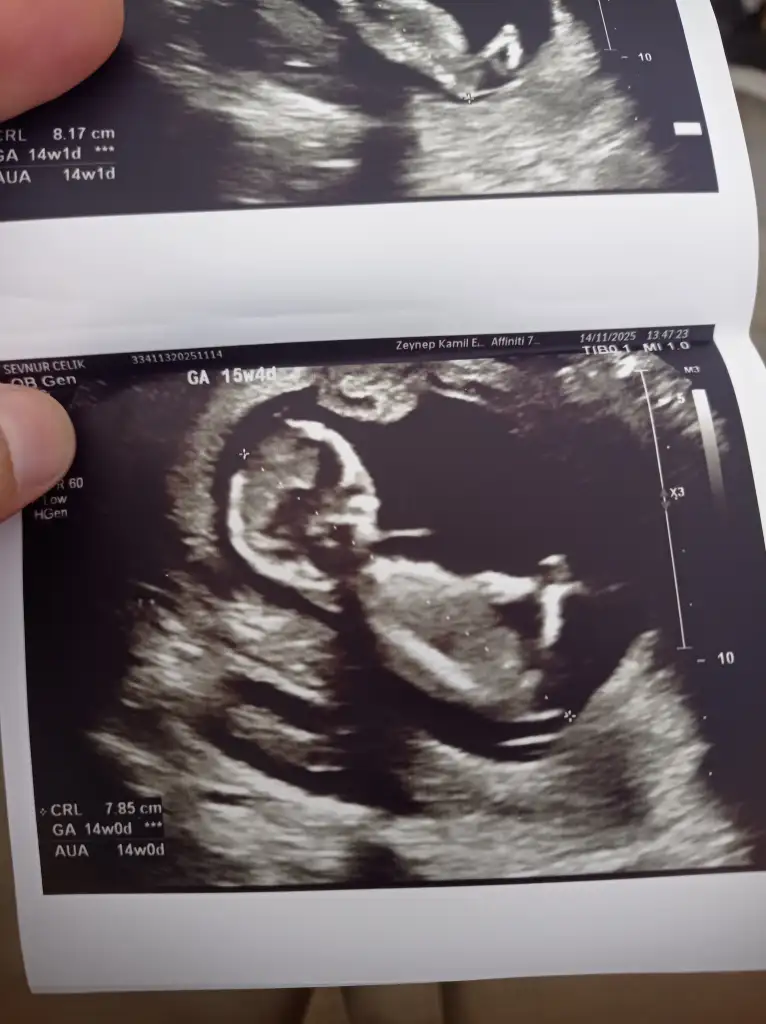

Ultrason görüntüsüne dayanarak gebeliğin yaklaşık 11. haftasında olduğunu görüyorum (aşağıda CRL ve GA bilgisi var). Bu haftalarda bebek henüz cinsiyetini ultrasonla güvenilir şekilde belli edecek kadar gelişmemiştir. Cinsiyet tahmini genellikle 13. haftadan itibaren daha net yapılabilir, ancak en doğru sonuçlar 16. haftadan sonra elde edilir.

1. hafta civarında “nub theory” (tüberkül teorisi) gibi yöntemlerle tahmin yapılmaya çalışılabilir ama bu yöntem bilimsel olarak kesin değildir ve yüksek hata payı içerir.

• Bu görüntüde cinsiyet tahmini yapmak şu an için mümkün değil.

• En doğru tahmin için birkaç hafta sonra tekrar ultrason yaptırmanız önerilir.